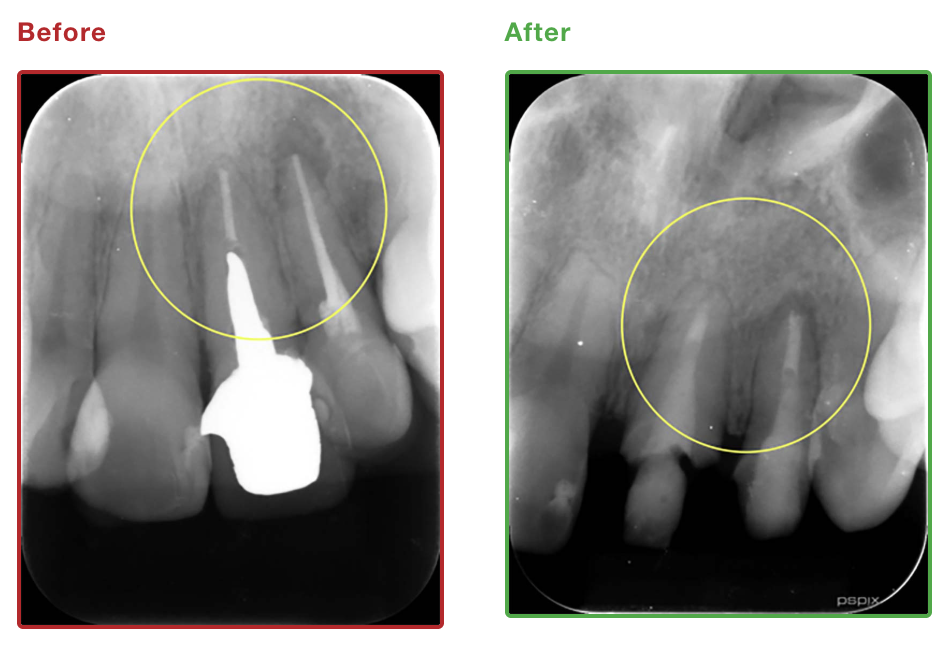

9.当院の症例

| 初診時年齢 | 40歳 |

|---|---|

| 主訴 | 根尖性歯周炎 |

| 抜歯/非抜歯 | – |

| 治療期間 | 2ヶ月 |

| 費用 | 10万円 |

| 治療のリスク | 術後に軽度の腫脹・疼痛の可能性 |

| 副作用 | – |

| 治療内容/装置 | 精密根管治療、矯正用プロビジョナル |